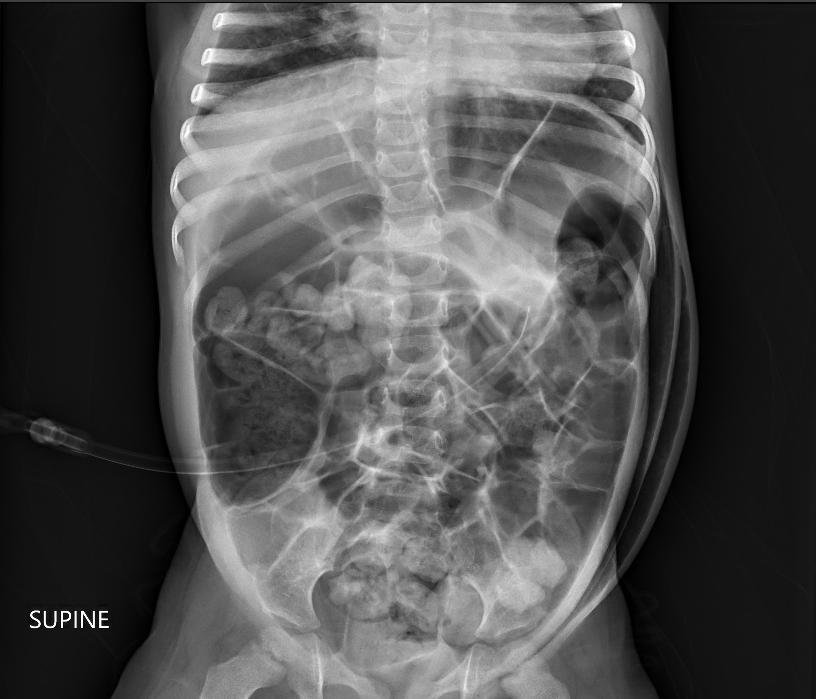

- GT complications are discussed including infection, peritonitis, bleeding (rare to need a transfusion), injury to adjacent organs, pneumoperitoneum (usually benign and transient), hypergranulation, cellulitis (often treated with a first-generation cephalosporin or topical mupirocin), dislodgement, tube migration, and buried bumper syndrome. For early dislodgement (especially first 4-6 weeks after placement), blind reinsertion should be avoided.